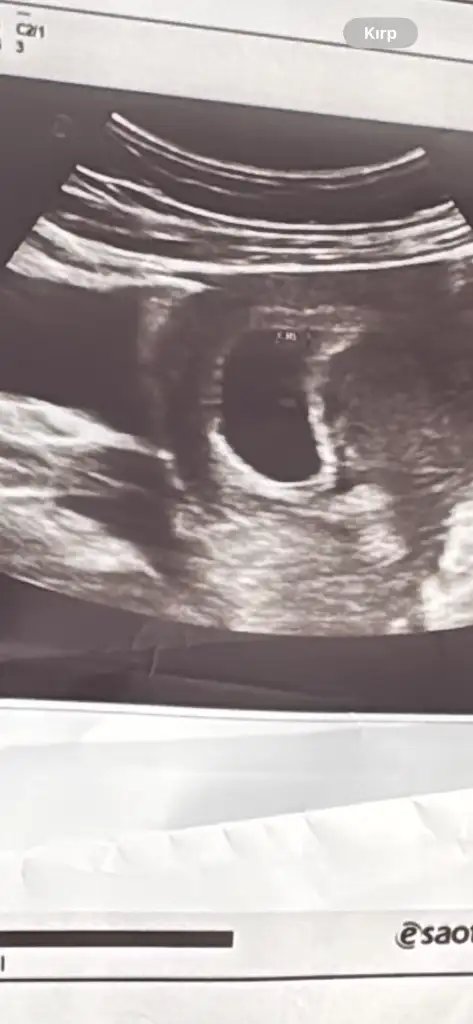

Kızlar herkese merhaba bende aranıza katıldım 🌸🌸

Bugün doktor kontrolüne gittik sat göre 7 +0 ama ultrasonda 6+2 çıktı herşey normal dedi .başta kalp atışını göremedi ama sonrasında gördük bende gördüm hatta . Herkesin hakkında hayırlısı olsun sağ Salim kucaklarımıza alalım inşallah 🌸🥰